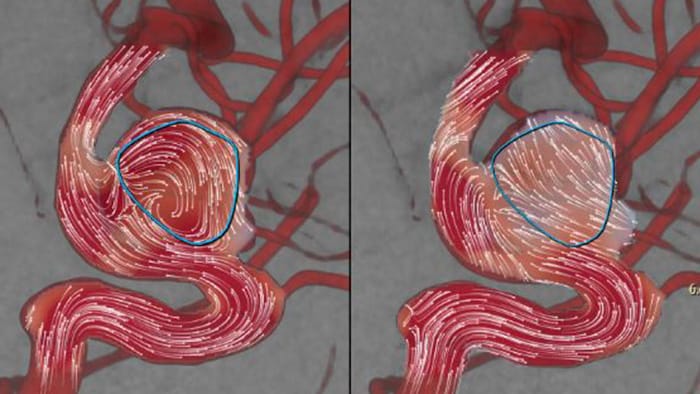

AneurysmFlow

Aneurysmflow blood flow diverter deployment

AneurysmFlow is designed to give you relevant information before and after flow diverter deployment. It visualizes and quantifies flow changes for greater confidence in procedural effectiveness.